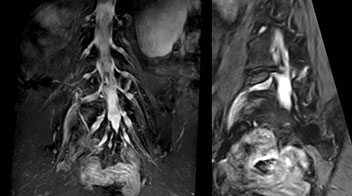

“The intra-luminal signal of veins, especially around the intervertebral space, can be suppressed well with NerveVIEW. As a result, we can easily observe the detailed nerve structure around the posterior ganglion,” he says. “This is why we use 3D NerveVIEW for intraforaminal stenosis and extraforaminal stenosis/herniation (lateral disc herniation). On the other hand, if herniation is suspected to exist inside the dorsal root ganglion (DRG), balanced TFE or ProSet-FFE is applied. NerveVIEW is not suitable for evaluating the median type of herniation.” The SE-EPI DWI-based method for MR neurography works well for large FOV exams like whole-body MRI, but focal examination of nerves is often limited by the attainable spatial resolution (both inplane and slice direction) and geometric distortion. “3D NerveVIEW achieves higher in-plane resolution – close to our other routine spine sequences – and the source images can be used instead of adding a fat-suppressed T2-weighted sequence,” Tanji says.

According to Tanji, methods such as ProSet FFE, STIR or 3D VISTA are anatomically nonselective because background signals, for instance from blood vessels, often interfere with nerves, which hampers evaluation of details, especially at the peripheral side of the nerves.

“Recently, the two surgical methods extreme and oblique lateral interbody fusion (XLIF and OLIF) have become mainstream for minimally invasive treatment of lumbar spinal canal stenosis and intervertebral foramen stenosis. With these surgical techniques, the spine is approached from the flank, and prior knowledge of the exact anatomy of the lumbosacral plexus would be extremely helpful. To that end, high slice resolution (less than 1 mm acquisition) that enables sharper sagittal MPR images will be needed.”

“For both brachial and lumbar plexus, we are currently using a 230 mm FOV and voxels of about 1 x 1 x 2 mm acquired (1 x 1 x 1 mm reconstructed). This provides us a good representation of the nerves, even though this FOV is relatively small. Regarding the inplane resolution, we hope to be able to bring that down to 0.7 mm, similar to our typical 2D multislice T2W images,” says Tanji.